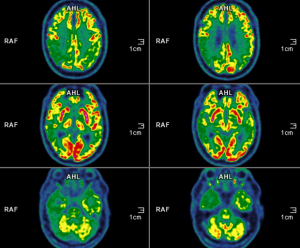

Qu’attendre de l’imagerie métabolique dans l’exploration des pathologies neurodégénératives de la personne âgée ?

L’imagerie métabolique est une technique d’imagerie fonctionnelle fondée sur la détection de traceurs radioactifs. Après injection intraveineuse, on obtient une cartographie 3D de la distribution du traceur. Cette imagerie donne…